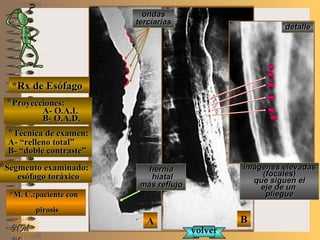

*Rx de Esófago*Rx de Esófago

**Proyecciones:Proyecciones:

A-A-

B-B-

**Técnica de examen:Técnica de examen:

**Segmento examinado:Segmento examinado:

*M. C.:paciente con*M. C.:paciente con

pirosispirosis

BBAA

A-A-El examen es normal o patológico?El examen es normal o patológico?

Examen patológico de esófago toráxico conExamen patológico de esófago toráxico con

técnica en A de relleno total y B de doble con-técnica en A de relleno total y B de doble con-

traste en proyecciones en A- O.A.I. y B- O.A.D.traste en proyecciones en A- O.A.I. y B- O.A.D.

B-B-La patología es congénita o adquirida?La patología es congénita o adquirida?

Patología adquiridaPatología adquirida

C-C- Dicha patología es orgánica, funcional o mixta?Dicha patología es orgánica, funcional o mixta?

Patología adquirida orgánicaPatología adquirida orgánica

D-D-La misma es neoplásica o no neoplásica?La misma es neoplásica o no neoplásica?

Patología adquirida orgánica no neoplásicaPatología adquirida orgánica no neoplásica

E-E-Puede describir la o las imágenes patológicas?Puede describir la o las imágenes patológicas?

Se identifica en A-una hernia hiatal axial, con re-Se identifica en A-una hernia hiatal axial, con re-

flujo gastroesofágico y ondas terciarias (pacienteflujo gastroesofágico y ondas terciarias (paciente

en decúbito) y en B-alteración del relieve inter-en decúbito) y en B-alteración del relieve inter-

no fino por la presencia de múltiplesno fino por la presencia de múltiples

imágenes elevadasimágenes elevadas UNTUNT focales (esofagítis porfocales (esofagítis por

reflujo)reflujo)NMNM **Opción avanzada para volver a ver las imágenes con reparosOpción avanzada para volver a ver las imágenes con reparos

A- O.A.I.A- O.A.I.

B- O.A.D.B- O.A.D.

A- “relleno total”A- “relleno total”

B- “doble contraste”B- “doble contraste”

esófago toráxicoesófago toráxico

herniahernia

hiatalhiatal

más reflujomás reflujo

imágenes elevadasimágenes elevadas

(focales)(focales)

que siguen elque siguen el

eje de uneje de un

plieguepliegue

volvervolver

ondasondas

terciariasterciarias

BB

AA

CC